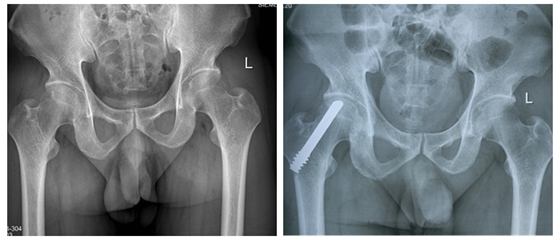

术前(左),术后(右)

患者术后第二天就可以站立